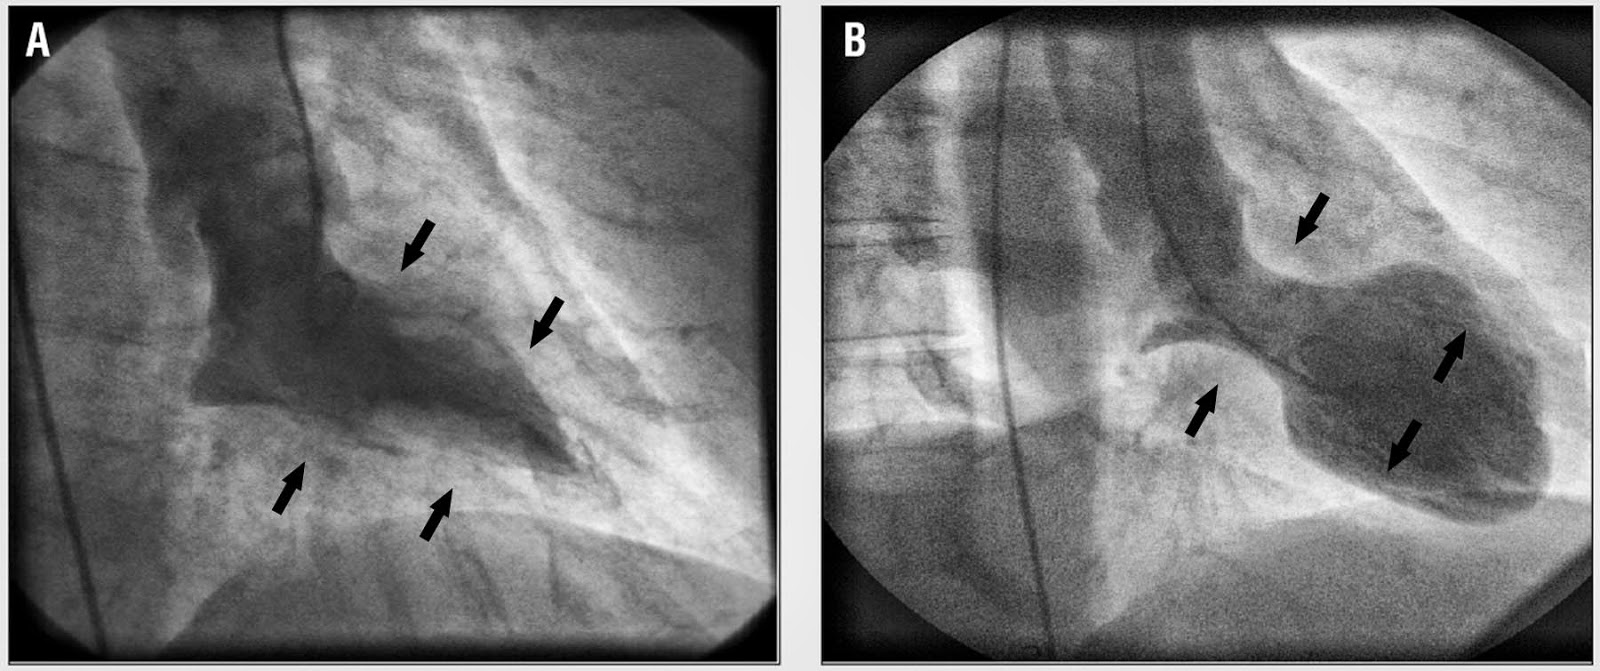

A ventriculografia esquerda demonstra balonamento apical (dilatação) com hipercinesia do segmento basal do ventrículo assim, lembrando a forma de um takotsubo (armadilha utilizada no Japão para pegar polvo).

Na imagem acima, podemos ver um coração normal durante a sístole (figura A) e um coração afetado, havendo contração apenas na base com dilatação do ápice (figura B), fazendo com que o coração assuma um formato semelhante à armadilha japonesa takotsubo.